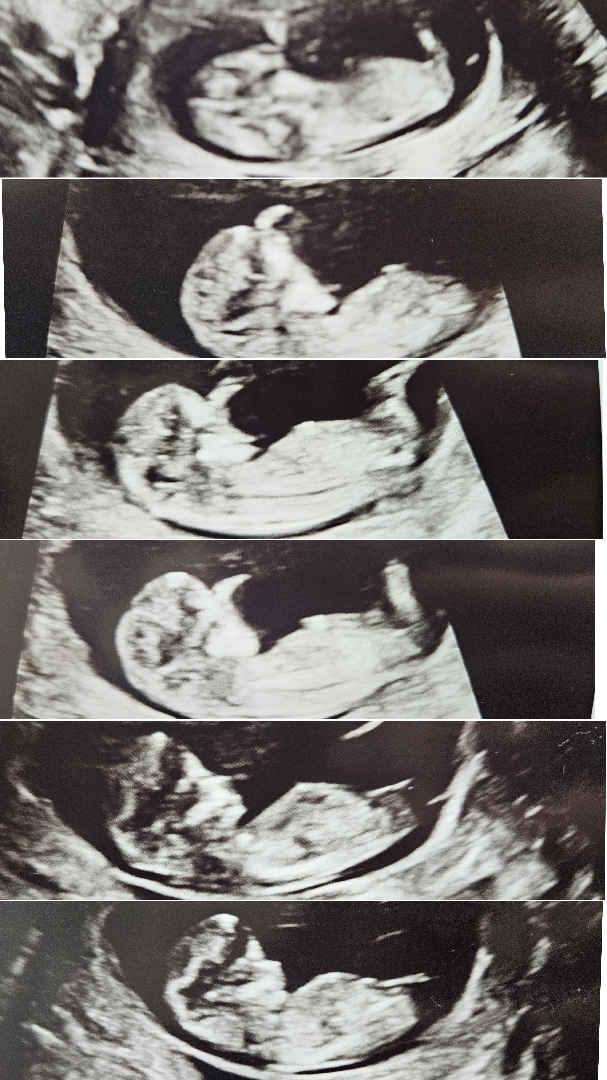

저도 각도법 한번 봐주시면 감사하겠습니다!!

봐도 전 잘 모르겠어요ㅠㅠ

각도는 딸인데 대가 길어서 아들같기도 하네요

오오...답변 감사합니다 대가 긴 편이군요..딸일지 아들일지..!!